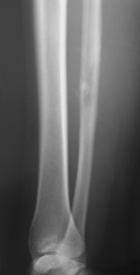

S.P. - 15 year old female presents with two month hx of right calf pain. Pain awakens her from sleep.